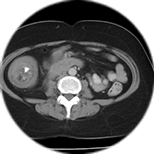

영상의학과는 MRI, CT, 초음파, X-ray 등 첨단 장비를 활용하여 신체 내부의 이상을 정밀하게 진단하고, 필요 시 영상 유도하에 조직검사나 중재시술도 시행합니다.

영상의학과는 각 과의 정확한 진료와 치료 방향을 결정하는 핵심 진단과로서, 뇌졸중, 암, 디스크, 장기 이상 등 다양한 질환의 조기 발견과 효율적인 치료 계획 수립에 중요한

역할을 합니다. 영상 판독은 영상의학과 전문의가 직접 수행하며,정확하고 신속한 결과 제공을 통해 환자의 회복을 돕습니다.

내부 질환 영상 진단